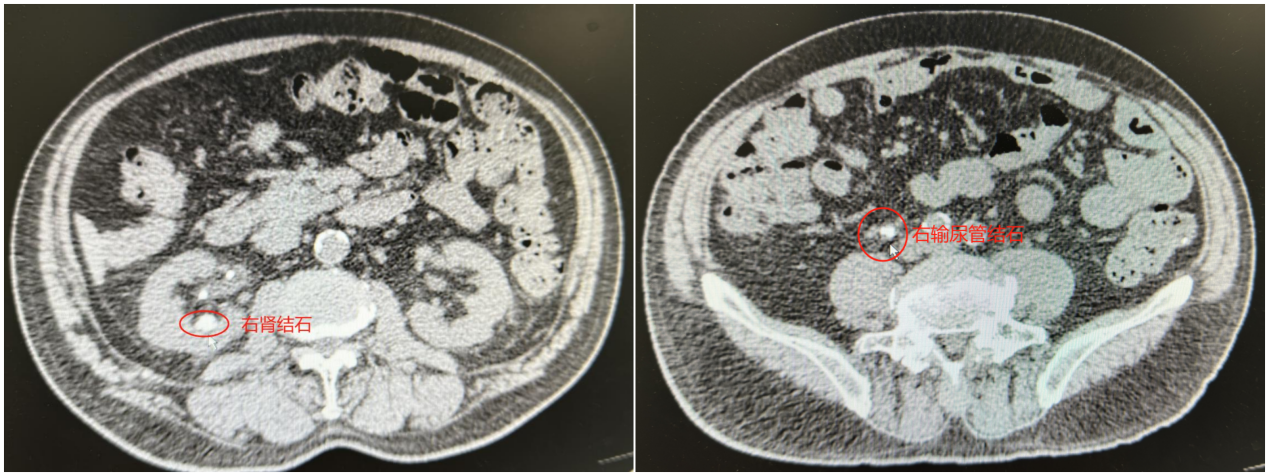

张老先生长期受高血压、糖尿病困扰,近日又因腰腹剧痛确诊为肾结石合并输尿管结石。经病友推荐,老人跨越半个北京城慕名找到北京市垂杨柳医院泌尿外科首席专家谷现恩。面对患者基础疾病多、肾功能受损风险高的复杂情况,谷现恩带领团队细致评估,最终决定采用创伤小、恢复快的经尿道输尿管软镜激光碎石术。

手术当日,谷现恩与泌尿外科主治医师王凯歌默契配合,借助先进的可弯曲输尿管软镜,在直径仅3毫米的腔道内精准定位结石。随着钬激光的精准发射,顽固结石被逐一粉碎,术中负压吸引彻底清理碎石。术后复查显示,患者体内结石完全清除,肾功能指标明显改善。